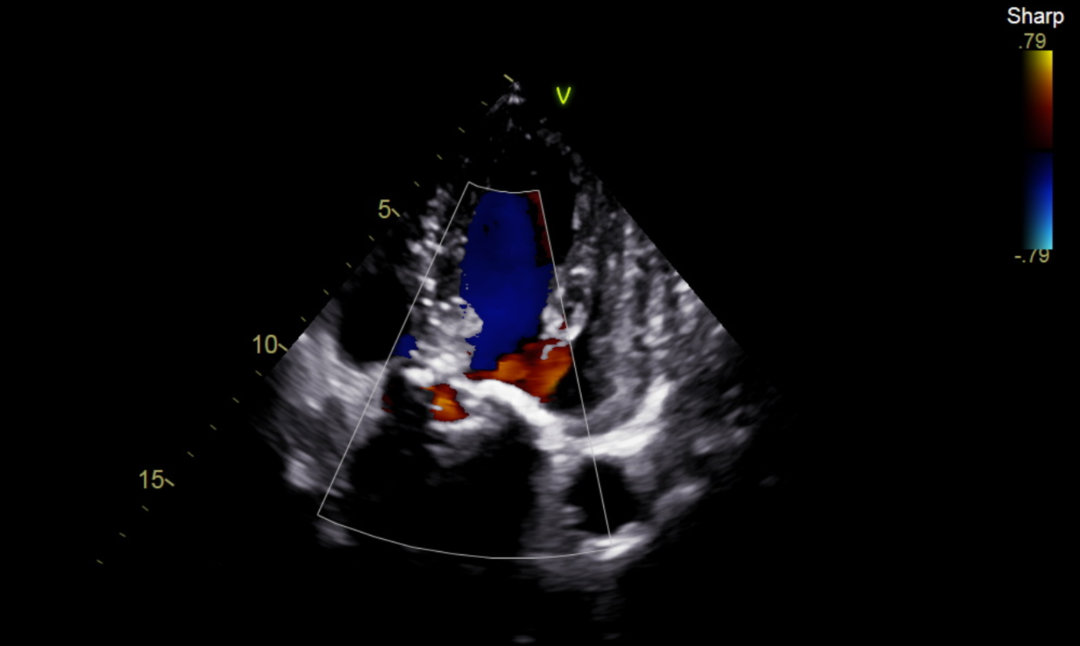

患者男性,78岁,术前心脏超声提示主动脉瓣重度狭窄伴轻度返流。CT评估结果显示三叶瓣,钙化均匀分布在三冠瓣,瓣环平均直径26.8mm,面积径25.7mm,左、右冠脉开口高度较高,无冠脉梗阻风险。下肢血管评估发现患者左侧髂外动脉瘤,下肢血管轻微钙化。